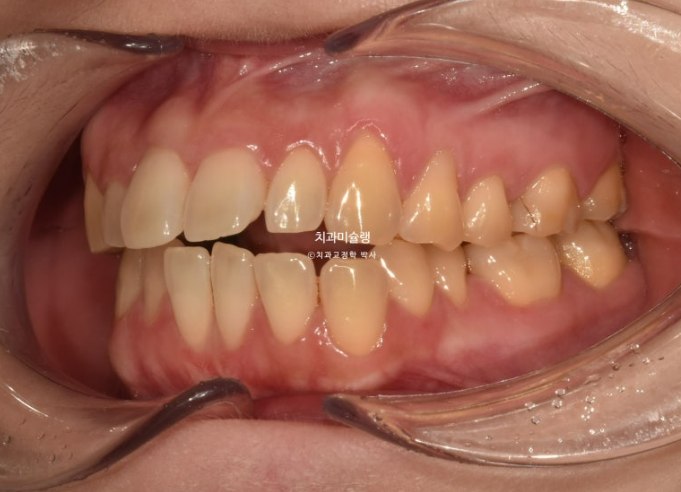

소구치에 윗니와 아랫니가 엇갈려 물리는 가위교합도 보입니다.

파란화살표는 가위교합 원인 치아입니다.

24.06